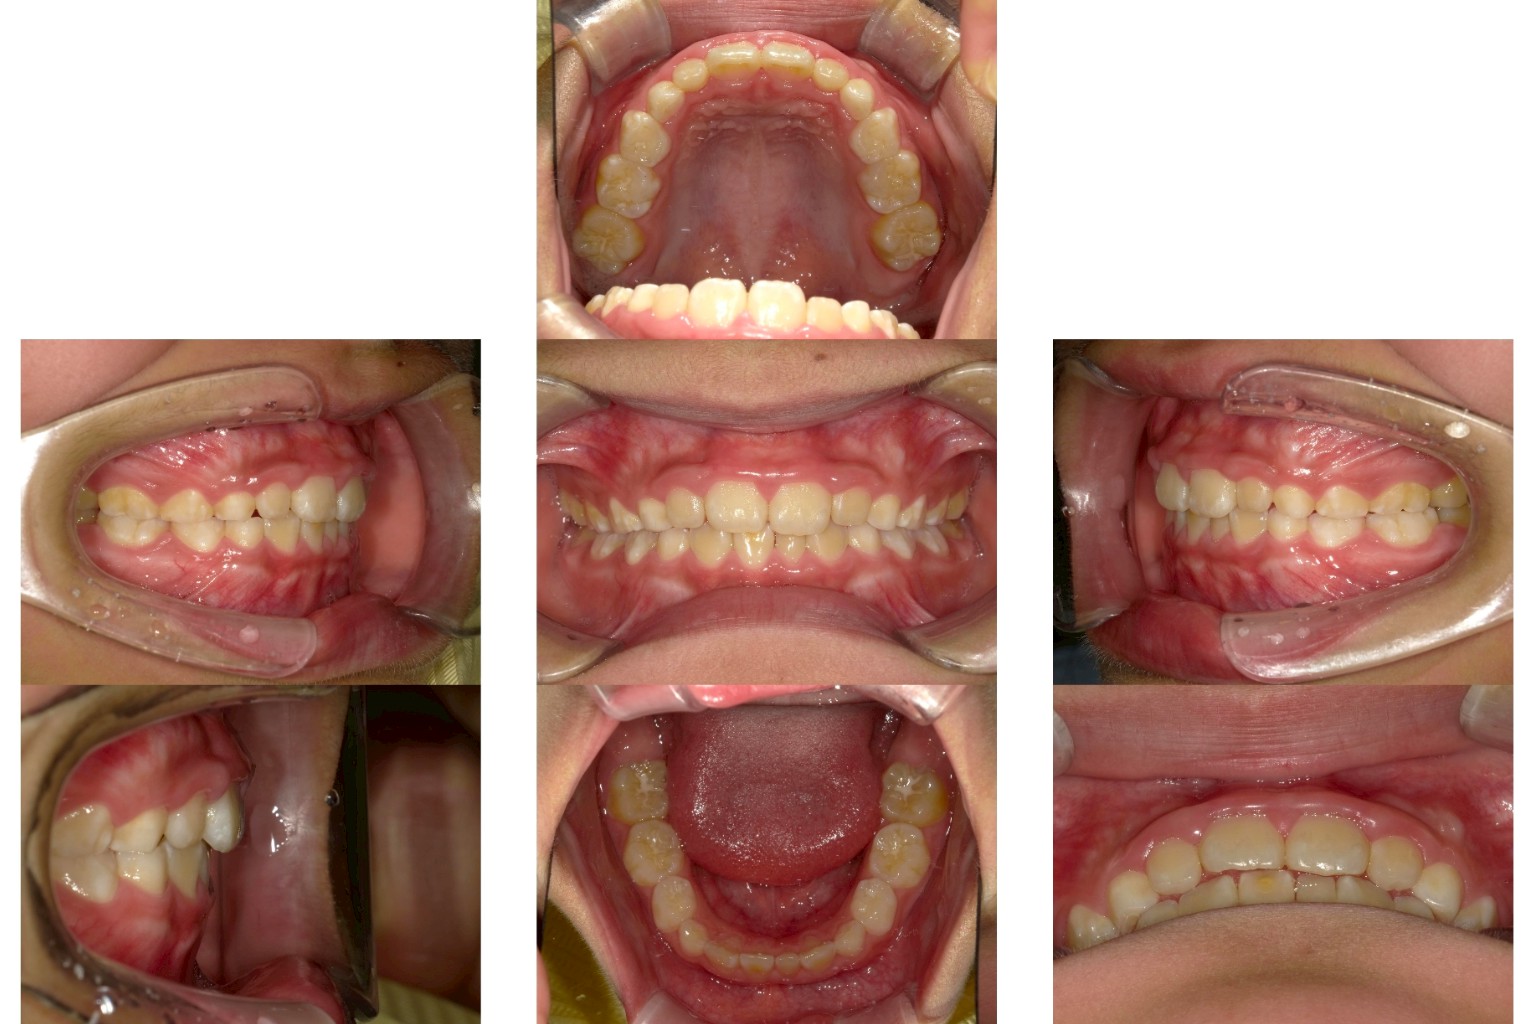

永久歯が乳歯の裏側に生えてきた

通常、永久歯は乳歯の真下から生えてきて、乳歯を自然に押し出すようにして生え替わります。しかし、中には乳歯が抜ける前に永久歯が内側(裏側)から生えてくるケースがあります。これを「二重歯列」とも呼びます。

前歯の生え変わり期(5〜7歳ごろ)に、乳歯がまだ残っているにもかかわらず、裏側から歯が生えてきているのを見つけたら、早めの歯科受診をおすすめします。上下どちらかの前歯で起きやすく、噛み合わせに影響を及ぼす場合もあります。

状態によっては、乳歯を早めに抜歯して、永久歯が自然な位置に移動できるようサポートします。また、必要に応じて、顎の成長を促す矯正装置や筋機能トレーニング(MFT)を組み合わせて、歯列の整った発育をサポートします。